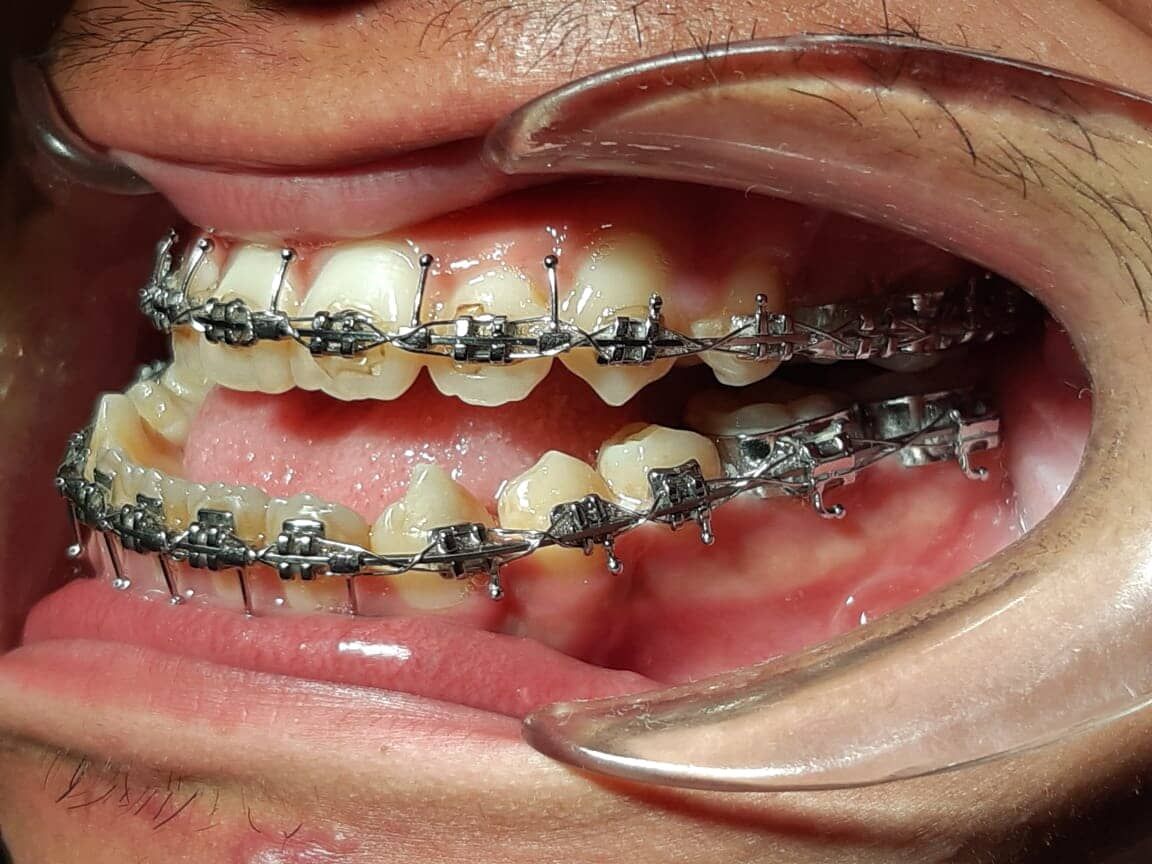

CIRUGÍA

ORTOGNÁTICA

Procedimientos quirúrgicos que son utilizados para corrección de trastornos en relación maxilomandibular, como reducción de prognatismo o retrognatismo mandibular y/o maxilar, mentoplastia de avance, retroceso y ascenso o descenso, los cuales generan un cambio tanto estético como funcional en los pacientes.

La cirugía tiene una duración de 3 horas aproximadamente, todas las incisiones son intraorales, evitando dejar alguna cicatriz visible en tu cara